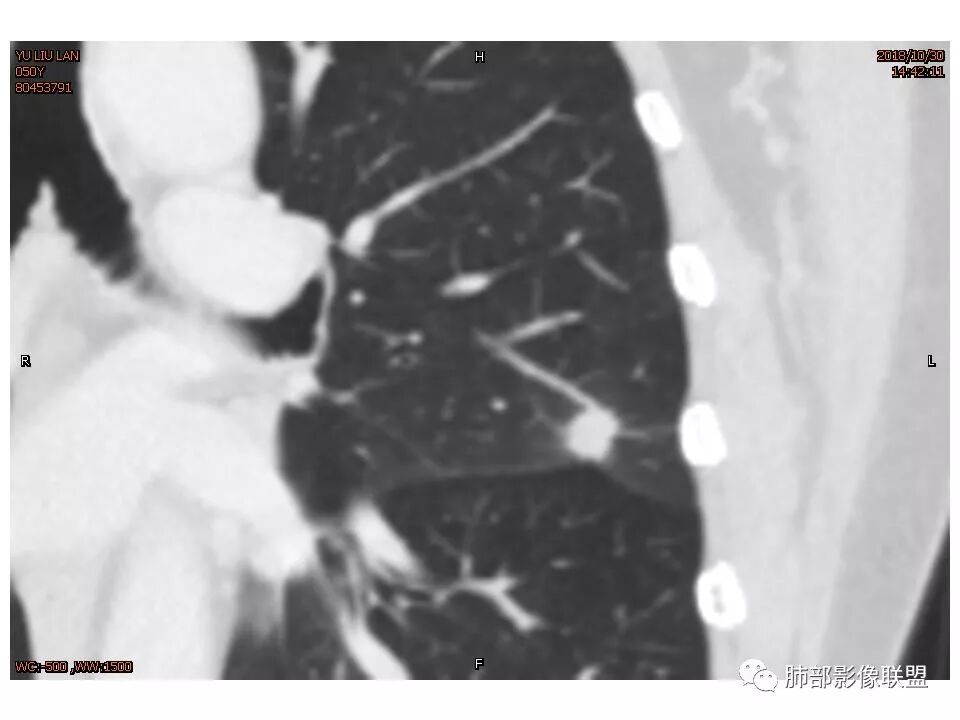

考虑恶性可能性大,毛刺分叶,局部膨隆。收缩明显,牵拉叶间裂

考虑恶性可能性大,毛刺分叶,局部膨隆,牵拉叶间裂收缩明显

因为南大说过实性病变有收缩力往往是慢性炎症。而腺癌毛玻璃才会牵拉叶间裂

有一些地方膨隆,肯定不放心,但是大部分还是平直收缩,要我读片我也炎症放前面,肺癌待排。但是现实生活我会建议切除

轴位像炎性,冠状、矢状位像恶性,真遇到了,纠结

1.胸膜下略不规则实性密度结节影,孤立,缺乏典型深分叶,可见淡薄边界模糊磨玻璃晕,可见相对细长软毛刺。

2.如南边老师分析,病灶缺乏边缘膨隆优势,甚至部分平直内收。

3.病灶收缩力不强,整体强化程度不显著。

4.综上,病灶更符合炎性,如隐球菌感染等,而不大符合肺腺癌。具体到机化性肺炎略有些出乎预料。